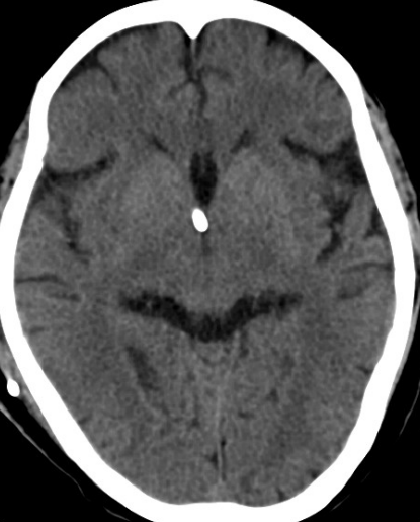

2014-11-28 CT

2015-12-13 MRI

2015-1-30 DSA